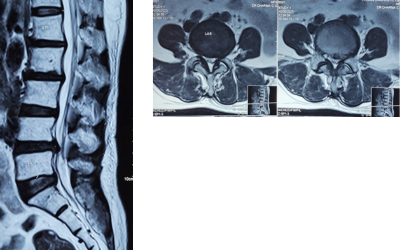

To confirm the diagnosis, we conducted an MRI scan of the lumbo-sacral spine and full spine. The imaging revealed:

L4-L5 disc prolapse with listhesis, showing disc herniation and vertebral slippage

Degenerative disc disease at L2-L3, indicating progressive disc wear

Old vertebral changes at L3, suggesting a past spinal injury

These spinal abnormalities clearly supported the need for immediate surgical slip disc treatment and lower back recovery, especially due to the structural compromise and risk of further spinal degeneration.